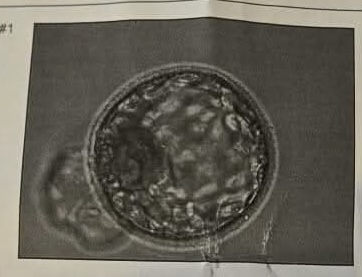

We’ve been quietly going through the process again since mid-last year, keeping our hopes high, but still appreciating that nothing about these bumpy roads is ever guaranteed.

It’s felt very different this time around, for a range of reasons. Firstly, we have our Ernie. We’ve been Dads for over three years now, and will be forever more. We’ve always felt we should be allowed to expand our family and give Ernie a sibling, just like any family with these desires, but with Ernie already part of our lives, that feeling of sheer desperation isn’t as strong (a very fortunate position to be in, we’ll add). Secondly, we know the process. We’ve felt better prepared, had fewer unknowns and were able to better brace ourselves for all the steps/costs/frustrations along the way. Thirdly, and incredibly significantly, we’re doing this with Erin again. Erin had always said to us she’d have a sibling for Ernie if it was something we wanted.